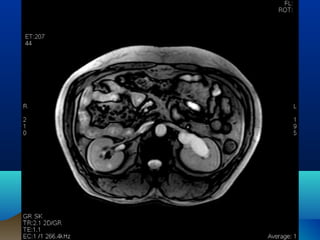

DIAGNOSISDIAGNOSIS

โ€ข MR UROGRAPHY

โ€ข TO DIFFERENTIATE PHYSIOLOGICAL FROM CALCULUS

โ€ข HYDRONEPHROSIS

โ€ข DOUBLE KINK SIGN โ€“ SPINDLE SHAPED PELVIC URETER